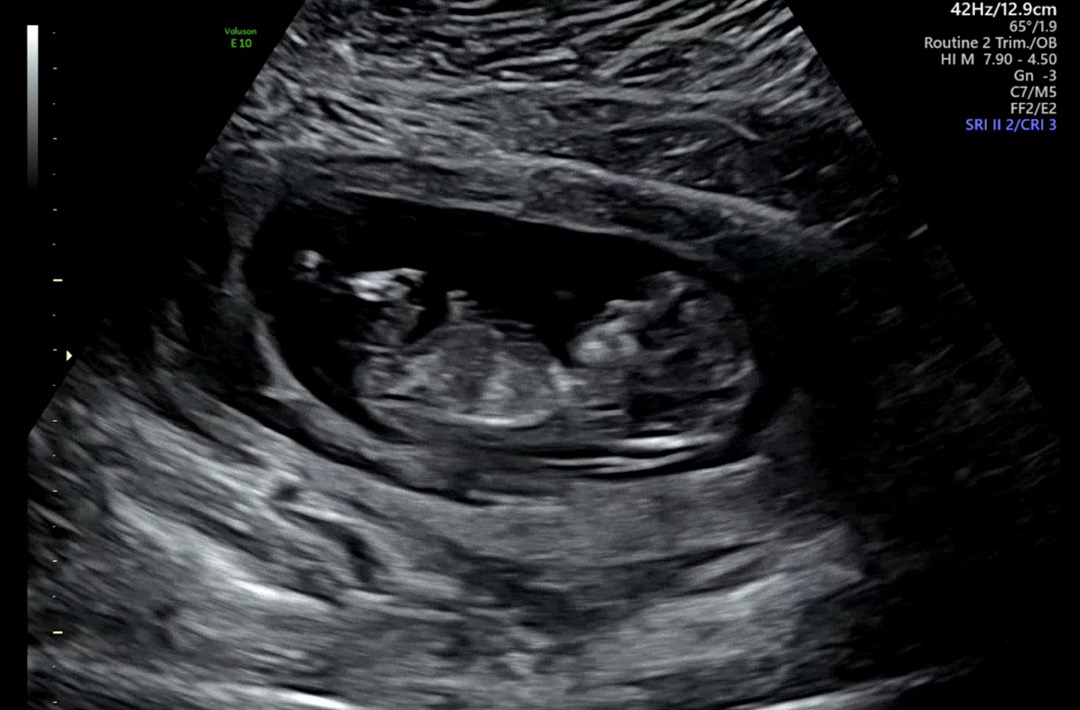

12주0일 초음파 보고 왔는데요! 저는 아무리봐도 잘 모르겠어요ㅠㅠ 딸일지 아들일지 아직 이르긴 하지만 고수님들의 고견 부탁드립니다🥹